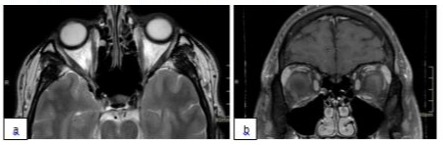

Incisional biopsy histopathology showed embryonal rhabdomyosarcoma, spindle cell type with high degree of malignancy. Microscopically the tumor consisted of hyperchromatic round to spindle shaped cells to round rhabdoblast, immunohistochemistry tests were positive for desmin, myogenin, vimentin and myoD1. The patient was referred to the medical oncology department. After staging, local disease was diagnosed with no metastasis, and he started with chemotherapy consisting of 9 cycles of IVA. After three IVA cycles, good response was noted with reduction in lid swelling clinically and demonstrated localized orbital tumor shrinkage. Then EBRT 50.4 Gy administered in 1.8 Gy fractions was done. During 12 years of follow-up, imaging MRI showed stable residual enhancement (Figure 4) with complete tumor remission. Last ophthalmic evaluation was normal with BCVA 0.8 (at tumor side) and no complaints.

Figure 4: MRI, axial(a) and coronal(b) section, last follow up MRI after treatment showing minimal medial residual enhancement in T2 with contrast.